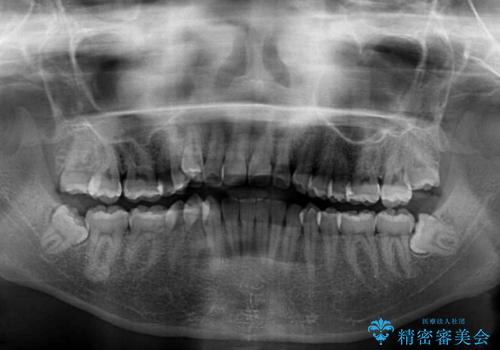

上顎歯列が下顎の歯列に対して狭小であり、一部下顎の奥歯が上顎よりも外側に位置している状態でした。

上顎の急速拡大装置を使用して上顎骨を側方に拡大することで上顎歯列を拡大し、下顎歯列も拡大できるようにすることで、歯列を整えることとしました。

歯列矯正では基本的に骨格を改善することはできませんが、急速拡大装置(MARPE)を使用することで上顎骨を側方に拡大させることができ、咬合状態を大きく改善することができます。